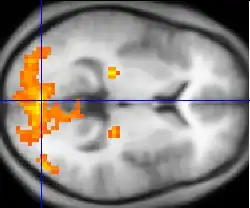

Consciousness is no longer thought to be a single thing that might be channeled into the brain by way of a tiny organ, like the pineal gland. Large parts of the human brain participate in the generation of many different types of conscious experiences. Some of the most well-studied parts of the brain with respect to their roles in consciousness are parts of the visual cortex. Damage to small parts of the visual cortex can selectively destroy conscious awareness of color, motion or even selectively remove one's ability to be consciously aware of faces as the unified wholes that we normally take for granted as social primates. Since the locus of consciousness is brain tissue, we can turn our attention to a detailed analysis of the biochemical processes of brain cells.